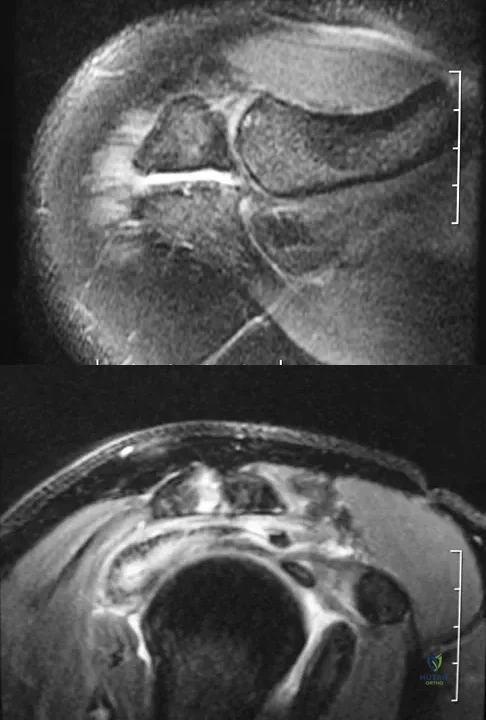

A 39-year-old man has anterior shoulder pain after landing on his abducted left shoulder while playing softball. Examination reveals a stable glenohumeral joint, pain on passive external rotation of greater than 25 degrees, and pain and weakness on belly press (Napoleon's) test. An MRI scan is shown in Figure 32. To provide maximum pain relief and return of function, management should include

Explanation